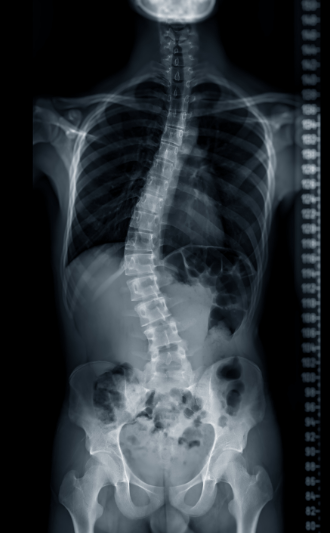

Living with scoliosis can bring challenges such as back pain, uneven posture, and limited mobility. But beyond the physical, scoliosis often affects how people feel about themselves. Changes in body shape, posture, or wearing a brace during formative years can deeply impact self-esteem and emotional health.

Yoga therapy offers a holistic, compassionate way to manage scoliosis, addressing both the body and the mind. Through mindful movement and exercises tailored to your unique curve, soft tissue release, breathwork, and self-awareness practices, you’ll not only find physical relief but also build confidence, resilience, and a deeper acceptance of your body.

Personalized practices tailored to different scoliosis patterns (C-curve, S-curve, thoracic, lumbar).